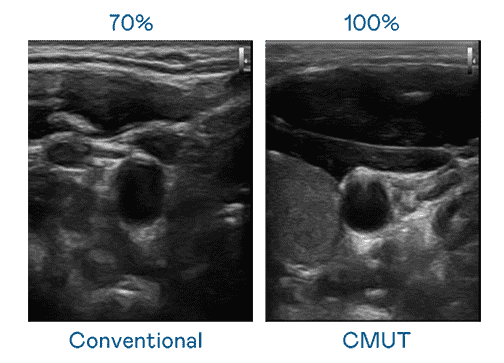

CMUT 技术是一种用电容式微机电元件来产生超音波讯号的技术。。。与传统 PZT 压电式技术相比,,CMUT 频宽增加 30%,,,,更宽频的超音波讯号让影像解析度大幅提升,,,是实现高影像品质医疗超音波扫描、、、促进精准医疗发展的关键技术。。。

超音波影像的解析度高低,,,,首先取决于探头能发出的讯号频宽。。。蓝狮在线 CMUT 可提供高清晰的超音波讯号,,,提供高频宽、、、高灵敏度、、影像纹理细节更高的超音波影像,,,协助医护人员缩短影像判读时间及利用精准的医疗影像进行诊断。。。。